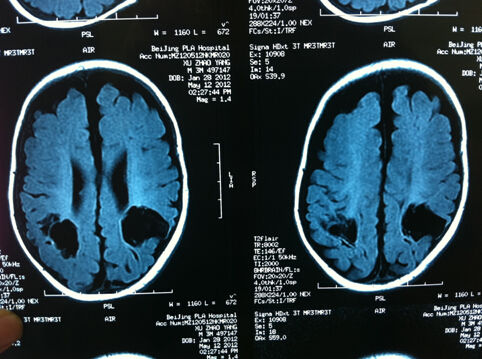

下面是宝宝的头颅核磁检片,脑内显示脑内有有两个缺损是软化灶,说明脑损伤严重。但这位宝宝通过早期干预,父母积极主动参与下,1岁半走得很好,智力也基本正常。这样的例子在宝篮贝贝中经常见到。

29周出生的早产宝宝,出生体重1.2kg,住院治疗54天。3月头颅核磁检查显示左额叶及双侧顶叶多发软化灶形成,这是由于颅内出血4度引起的脑软化灶。